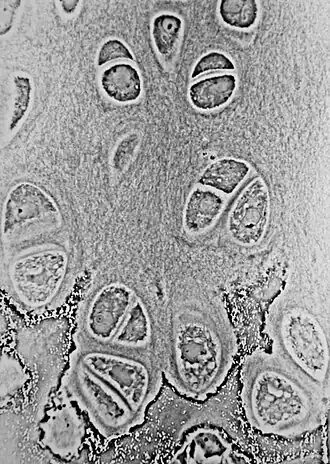

![]() Light micrograph of undecalcified hyaline cartilage showing chondrocytes and organelles, lacunae and matrix. | |